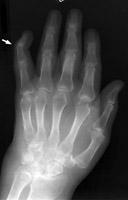

Swan Neck Deformity

Rheumatoid arthritis

Among the many osseous abnormalities that may be seen in Rheumatoid Arthritis, the swan neck deformity is the culmination of multiple abnormalities in the hand. Specifically, the deformity arises from hyperextension of the proximal interphalangeal joint, while the distal interphalangeal joint is flexed.